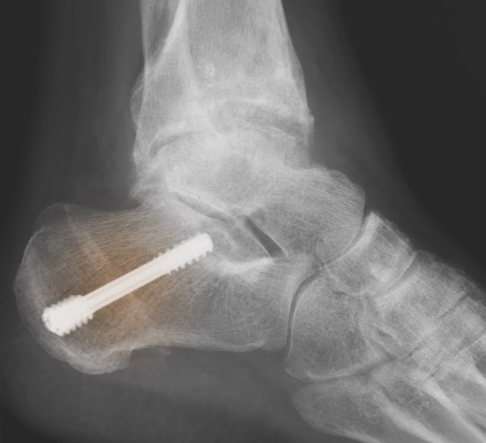

Fersenbeinumstellung bei Hohlfuß

Eine der am häufigsten durchgeführten knöchernen Korrekturen des Hohlfußes ist die sogenannte Fersenbeinosteotomie. Diese Umstellungsoperation ersetzt die regelmäßig beobachtete Varusstellung des Fersenbeins, das Abknicken nach innen, durch eine regelrechte Stellung des Fersenbeins. Auch der Ansatz der Achillessehne und der Verlauf der Beinachse im Rückfuß werden korrigiert: Der Sehnenzug der Achillessehne ist nach der Umstellung wieder konform mit dem Verlauf der Beinachse im Rückfuß.

Die Korrektur der Fersenbeinstellung führt somit auch zu einer Begradigung des Sprungbeins in der Sprunggelenksgabel. Damit beugt die Fersenbeinumstellung einer Arthrose im Sprunggelenk vor. Die Operation des Ansatzes der Achillessehne am Fersenbein normalisiert somit auch die Funktion der Achillessehne und der Wadenmuskulatur. Auch eine Haglundferse - eine schmerzhafte Veränderung von Weichteilen und Knochen des oberen Fersenbeines - kann auf diese Weise verhindert werden, weil der Druck des Schuhs auf das Fersenbein deutlich abnimmt.

Die Korrektur des Fersenbeins verbessert zudem die motorischen Fähigkeiten des Patienten. Die Neigung zu Umknickverletzungen ist reduziert und die Gangsicherheit nimmt zu. Langfristig reduziert sich die Belastung für die Außenbänder des Sprunggelenks.

Der nach Fersenbeinumstellung flachere Rückfuß senkt das Fußlängsgewölbe spürbar ab. Die Verdrehung des Rückfußes gegenüber dem Vorfuß verringert sich.